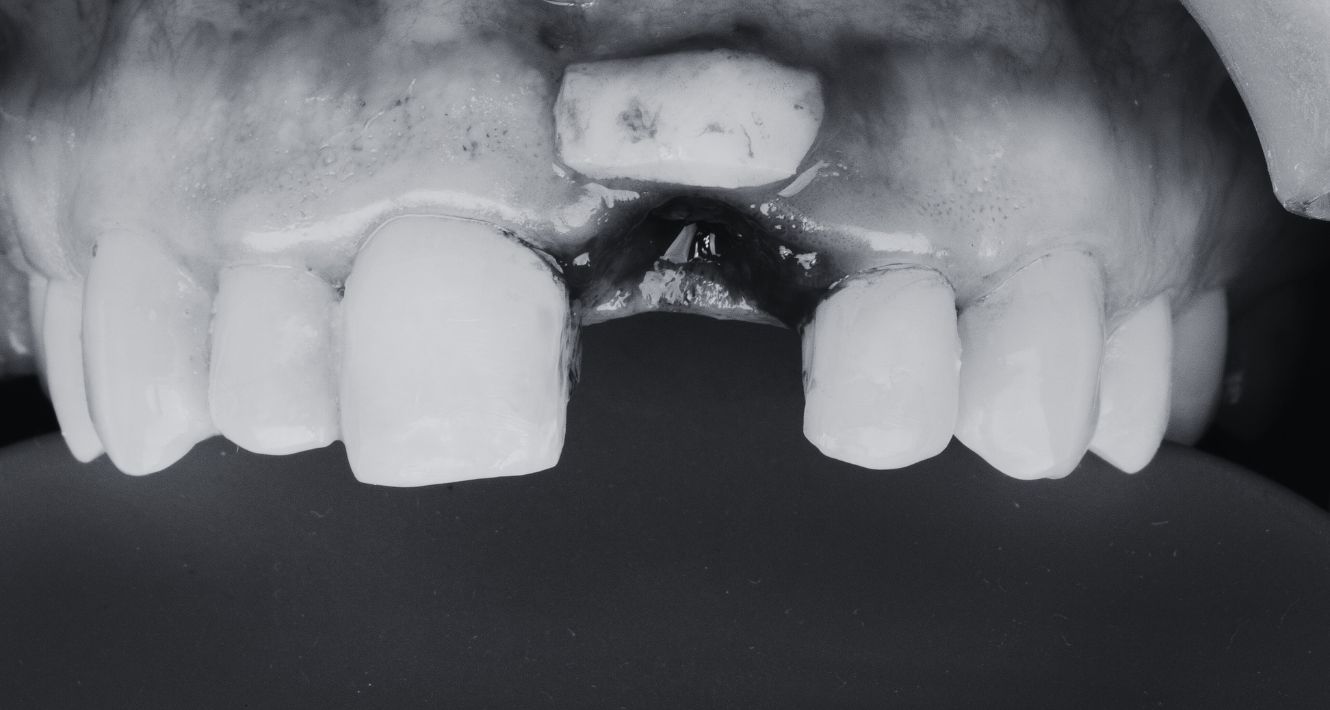

Le principe de la greffe osseuse est assez simple en théorie : il s’agit d’ajouter ou de restaurer l’os dans une zone spécifique de la mâchoire. Cela se fait soit en prélevant de l’os d’une autre partie du corps du patient, soit en utilisant des substituts osseux. Mais pourquoi est-ce si important en implantologie ?

Après la perte d’une dent : Chaque dent joue un rôle crucial dans la stimulation de l’os de la mâchoire. Lorsqu’une dent est perdue, cette stimulation disparaît, ce qui peut entraîner une atrophie osseuse. Si le patient souhaite un implant des années après avoir perdu une dent, il se peut qu’il n’ait pas suffisamment d’os pour soutenir l’implant. C’est ici qu’intervient la greffe osseuse.

Face à la parodontite : Cette maladie des gencives, si elle n’est pas traitée, peut ravager l’os entourant les dents. Si des dents affectées doivent être remplacées par des implants, il est souvent nécessaire de reconstruire d’abord l’os perdu.

Après un traumatisme ou une infection : Les accidents ou les infections sévères peuvent parfois entraîner la perte d’une partie significative de l’os de la mâchoire. Avant d’envisager des implants, il est essentiel de reconstruire cet os.